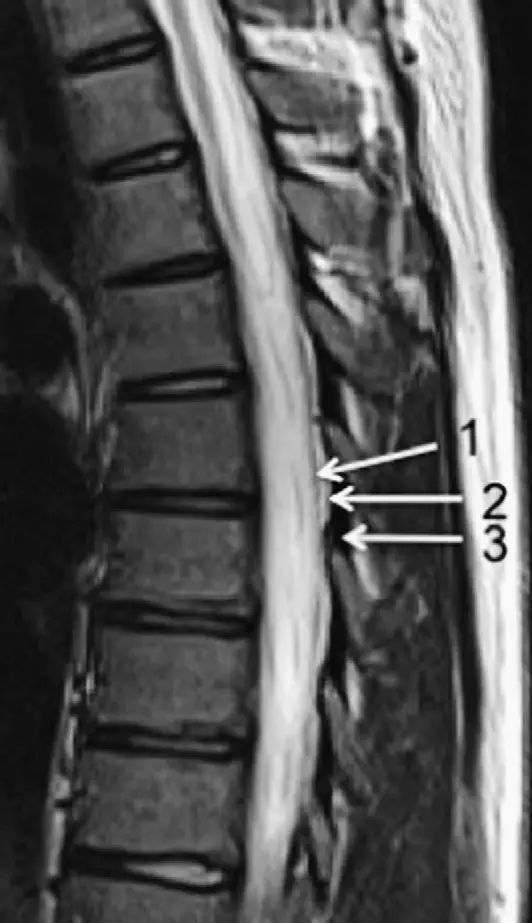

图1正常脊椎的MRI检查,左图为正中矢状位T2WI,右图为T1WI图 2 胸椎 T2WI 轴位图:1,肋椎关节;2,类骨头;3,黄韧带;4,椎弓根;5,椎弓板;6,横突;7,棘突;8,肋横突关节;9,肋结节;10,半奇静脉;11,后纵韧带图 3 腰椎矢状位 T1WI 序列成像:1,脊髓;2,脊髓圆锥;3,马尾;4,蛛网膜下腔;5,硬膜外脂肪;6,黄韧带;7,棘间韧带;8,棘上韧带;9,椎体静脉丛;10,硬膜外静脉丛;11,硬膜外脂肪;12 主动脉图 4 L5/S1 水平轴位 T1WI 序列成像:1,腰肌;2,L5 神经根(前支);3,L5 神经根(后支);4,黄韧带;5,蛛网膜下腔;6,马尾神经根;7,小关节面;8,髂腰韧带;9,左髂外静脉;10,左髂外动脉;11,右髂外动脉;12,右髂外静脉;13,多裂肌;14,竖脊肌组图 5 腰椎旁矢状位 T1WI 序列成像:1,腰静脉;2,腰动脉;3,椎间孔静脉;4,脊神经节后根;5,椎间孔静脉;6,关节面;7,多裂肌;8,竖脊肌群;9,胸腰筋膜,后层图 6 胸椎 T1WI 序列成像:1,胸髓;2,蛛网膜下腔;3,硬膜外脂肪;4,黄韧带;5,多裂肌;6,棘突;7,硬膜外静脉;8,棘上韧带图 7 胸椎矢状位 T2WI 序列成像:1,胸髓;2,蛛网膜下腔;3,黄韧带;4,多裂肌;5,棘突;6,棘上韧带;7,椎体静脉;8,脊髓圆锥;9,马尾图 8 胸椎旁矢状位 T2WI 序列成像:1,硬膜囊后壁;2,硬膜外脂肪;3,黄韧带图 9 胸椎轴位 T2WI 序列成像:1,主动脉;2,半奇静脉;3,奇静脉;4,椎间孔静脉;5,胸肋间血管;6,脊神经节后根;7,椎体静脉;8,后纵韧带;9,脑脊液流动伪影;10,多裂肌;11,背最长肌;12,斜方肌图10 胸椎旁矢状位 T2WI 序列成像:1,椎间孔静脉;2,胸椎旁肋间动静脉;3,神经根;4,上关节突;5,下关节突;6,关节面;7,椎弓峡部;8,椎弓根;9,黄韧带;10,竖脊肌群;11,斜方肌——本期完——